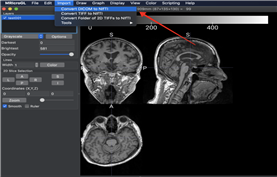

| 뇌영상 데이터 | ![]() |

뇌영상 데이터 가공과 동일